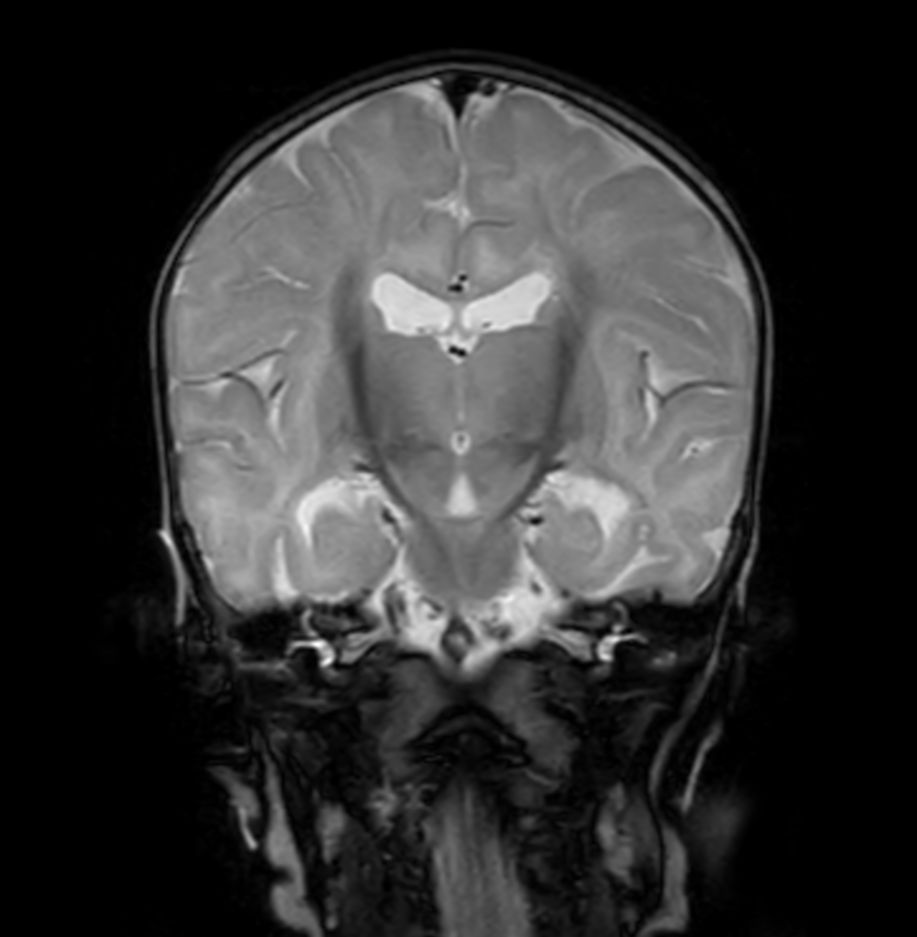

Coronal T2w TSE with ComforTone